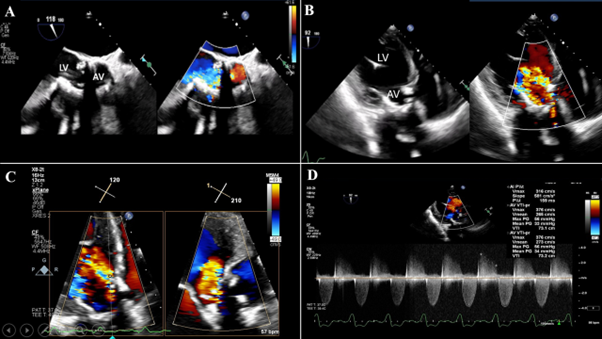

A transoesophageal echocardiogram (TEE) revealed severe left ventricular (LV) dysfunction with an LV ejection fraction (LVEF) of 25%, severe transvalvular AR, and moderate-to-severe prosthetic aortic stenosis (Figure 1, Video 1). The Heart Team recommended a redo-TAVR due to extreme operative risk. Cardiac computed tomography revealed an under-expanded Sapien XT (perimeter 61.3 mm, area 298 mm2 at valve midframe). A 23-mm Evolut FX valve (Medtronic) was chosen for the redo-TAVR.